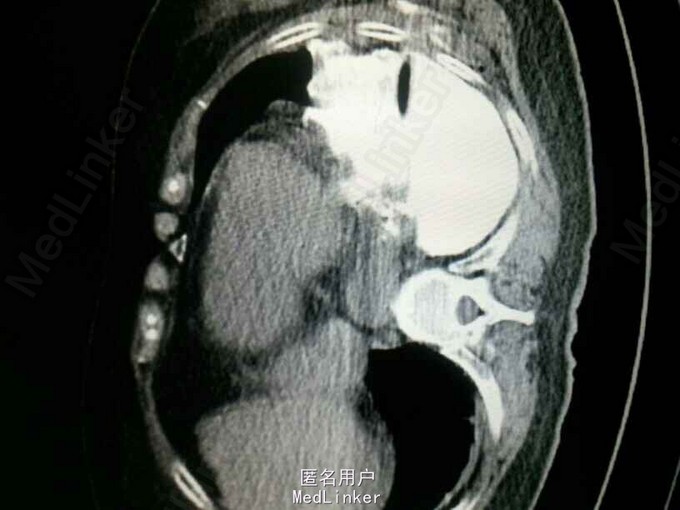

查体:气管居中,左肺呼吸音弱,右肺呼吸音尚可。未闻及湿啰音。胸腔引流管可见褐色浑浊液体引出。 腹部CT肝脾胰未见异常,胆总管扩张。 食管造影:食管下端撕裂,食管胸膜瘘。 胸CT左肺气胸,左侧胸腔内高密度影,考虑造影剂漏入胸腔。左肺实变,右侧少量胸腔积液。

诊断:自发性食管破裂。 治疗:急诊行胸腔闭式引流。后行左剖胸食管破裂修补。术中见胸腔污染严重,见菜叶,消化液等。后纵膈可见较多脓性分泌物,食物残渣,坏死组织。食管裂口处上方可见5cm纵向肌层及粘膜层撕裂口,相应位置处可见纵膈胸膜撕裂口。术后予肠内肠外营养,舒普深,泰能,稳可信,抗感染,术后反复行2次食管造影,仍存在食管破裂口,术后一月行胃镜及食管支架植入术。第二天行进食流质及半流质通畅,平稳出院。